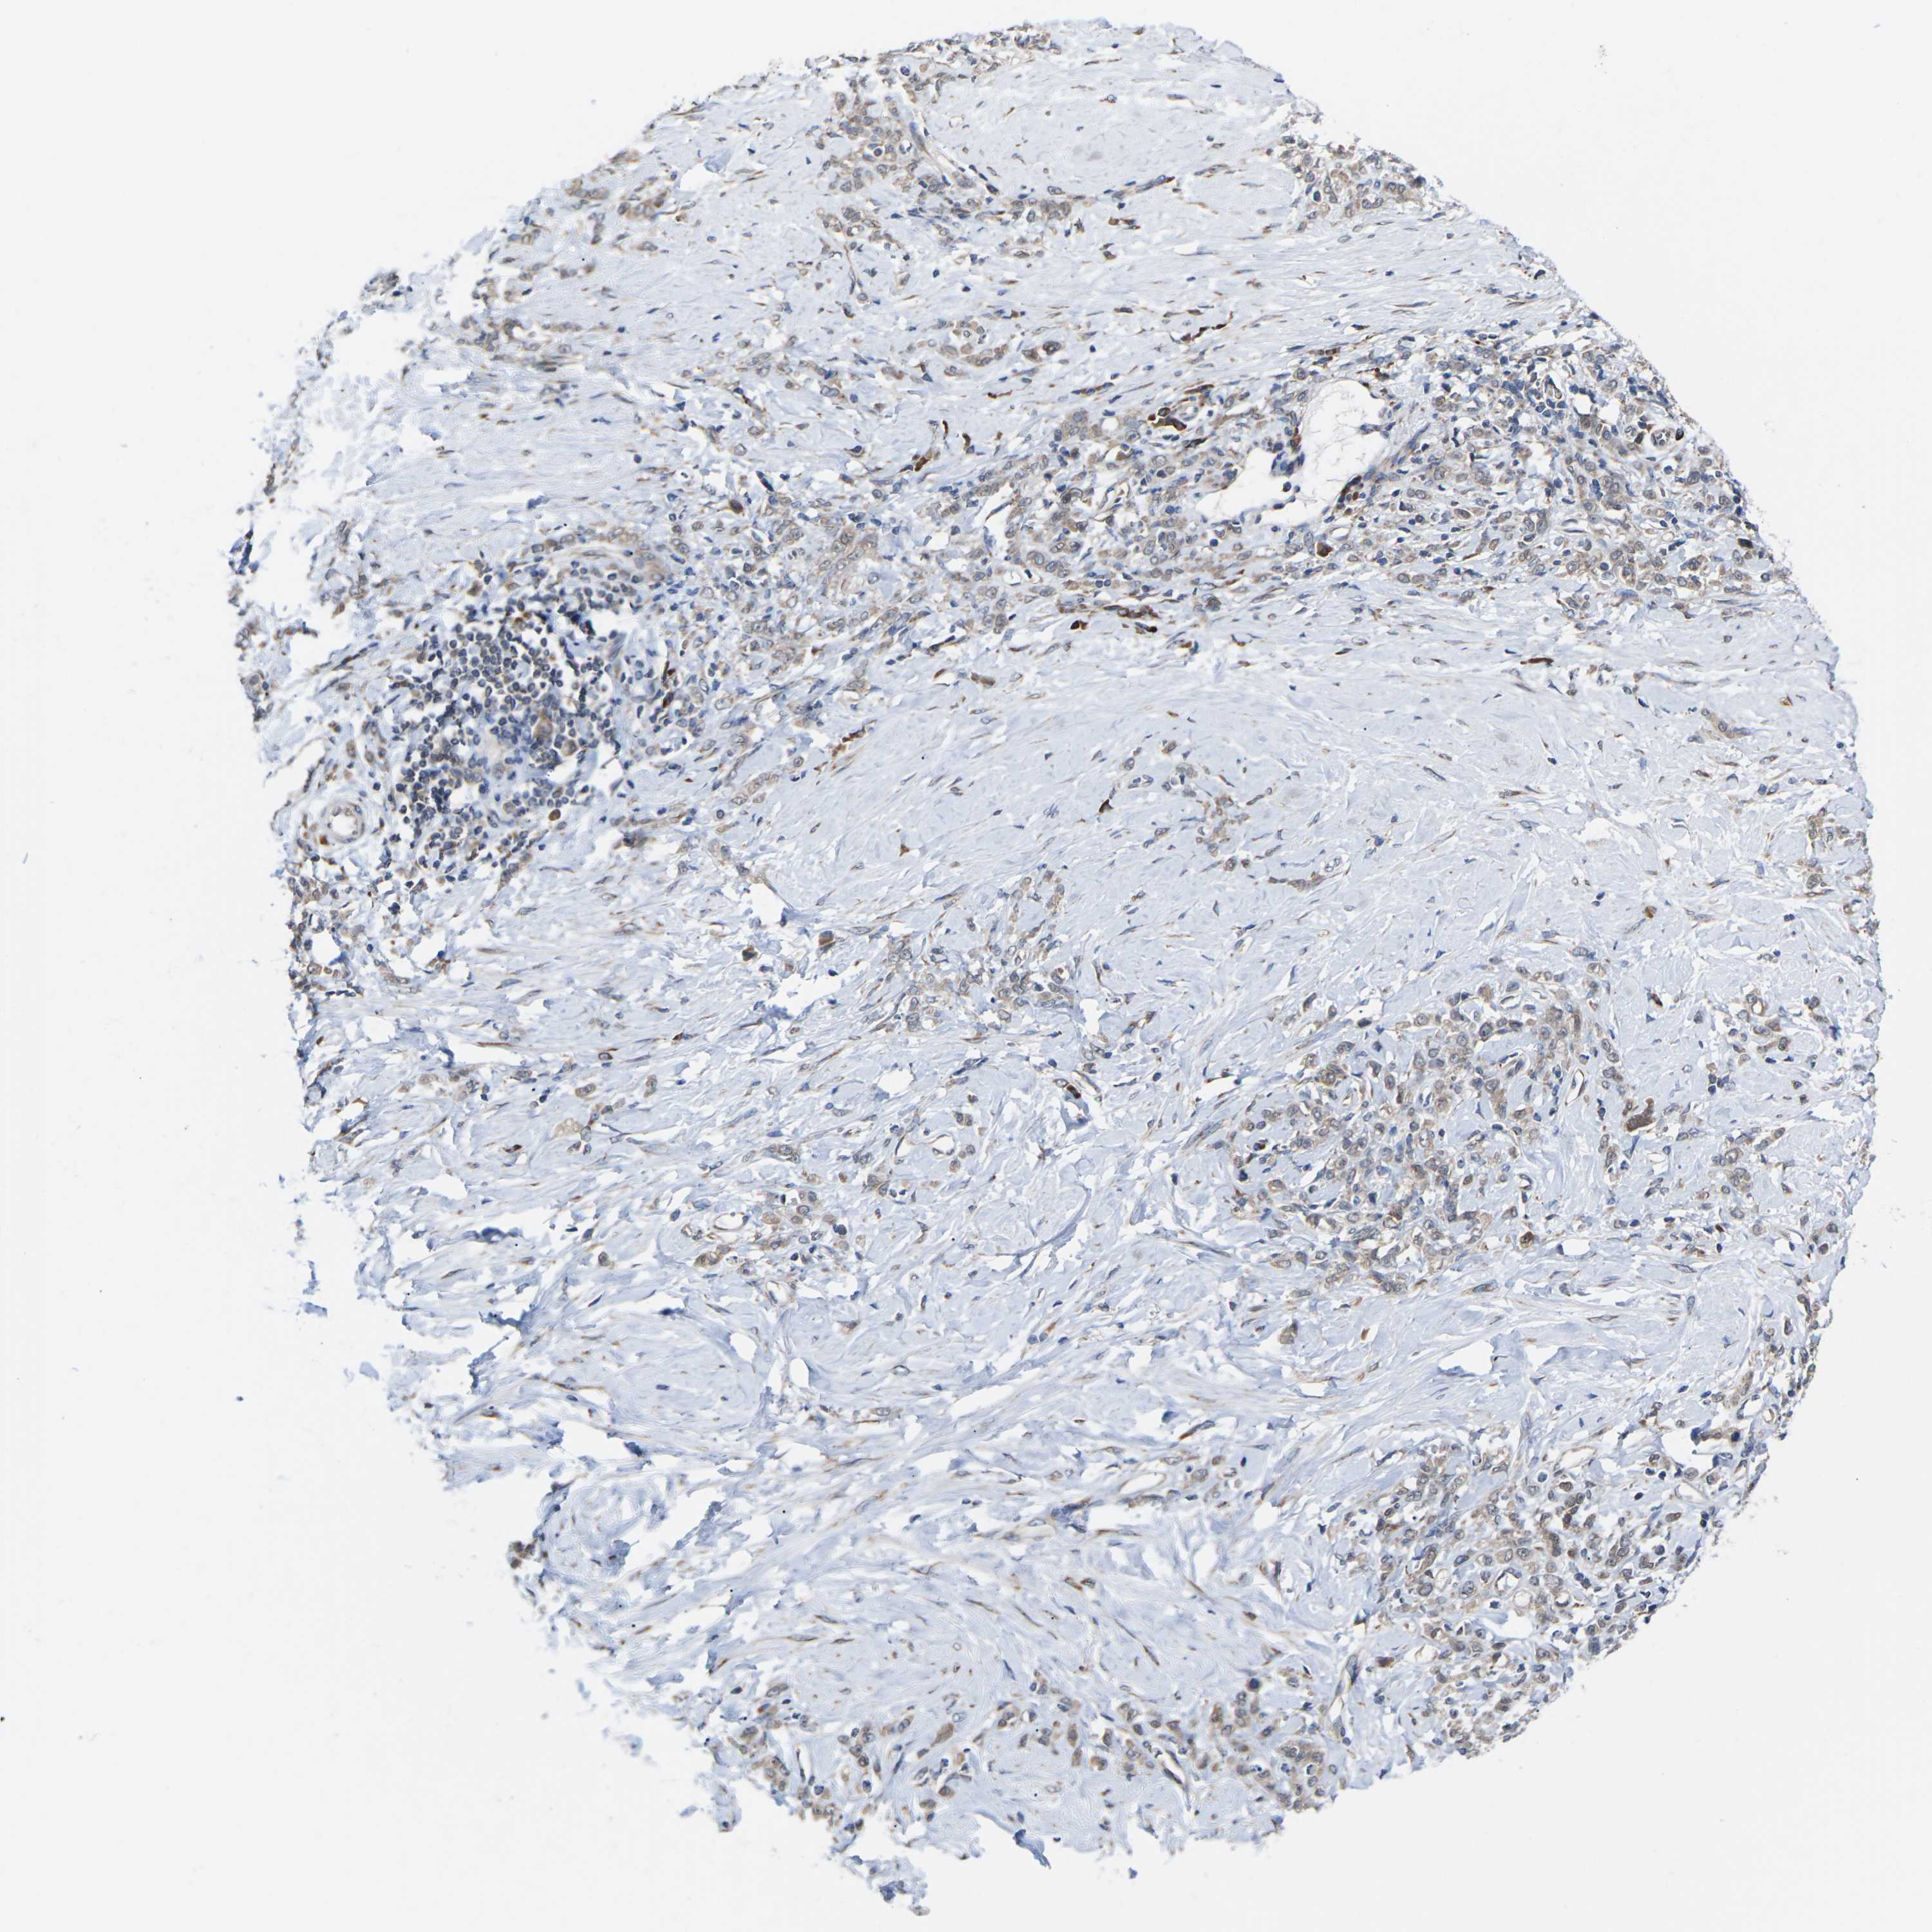

STOMACH CANCER - Protein expressioni

A mouse-over function shows sample information and annotation data. Click on an image to view it in a full screen mode. Samples can be filtered based on level of antibody staining by selecting one or several of the following categories: high, medium, low and not detected. The assay and annotation is described here.

Note that samples used for immunohistochemistry by the Human Protein Atlas do not correspond to samples in the TCGA dataset.

Antibody stainingi

Antibody staining in the annotated cell types in the current human tissue is reported as not detected, low, medium, or high, based on conventional immunohistochemistry profiling in selected tissues. This score is based on the combination of the staining intensity and fraction of stained cells.

Each image is clickable and will lead to virtual microscopy that enables deeper exploration of all samples and also displays staining intensity scores, fraction scores and subcellular localization as well as patient and tissue information for each sample.

Antibody HPA014907

Staining

High

Medium

Low

Not detected

Intensity

Strong

Moderate

Weak

Negative

Quantity

>75%

75%-25%

<25%

None

Location

Nuclear

Cytoplasmic/membranous

Cytoplasmic/membranous,nuclear

Adenocarcinoma, NOS

Adenocarcinoma, High grade